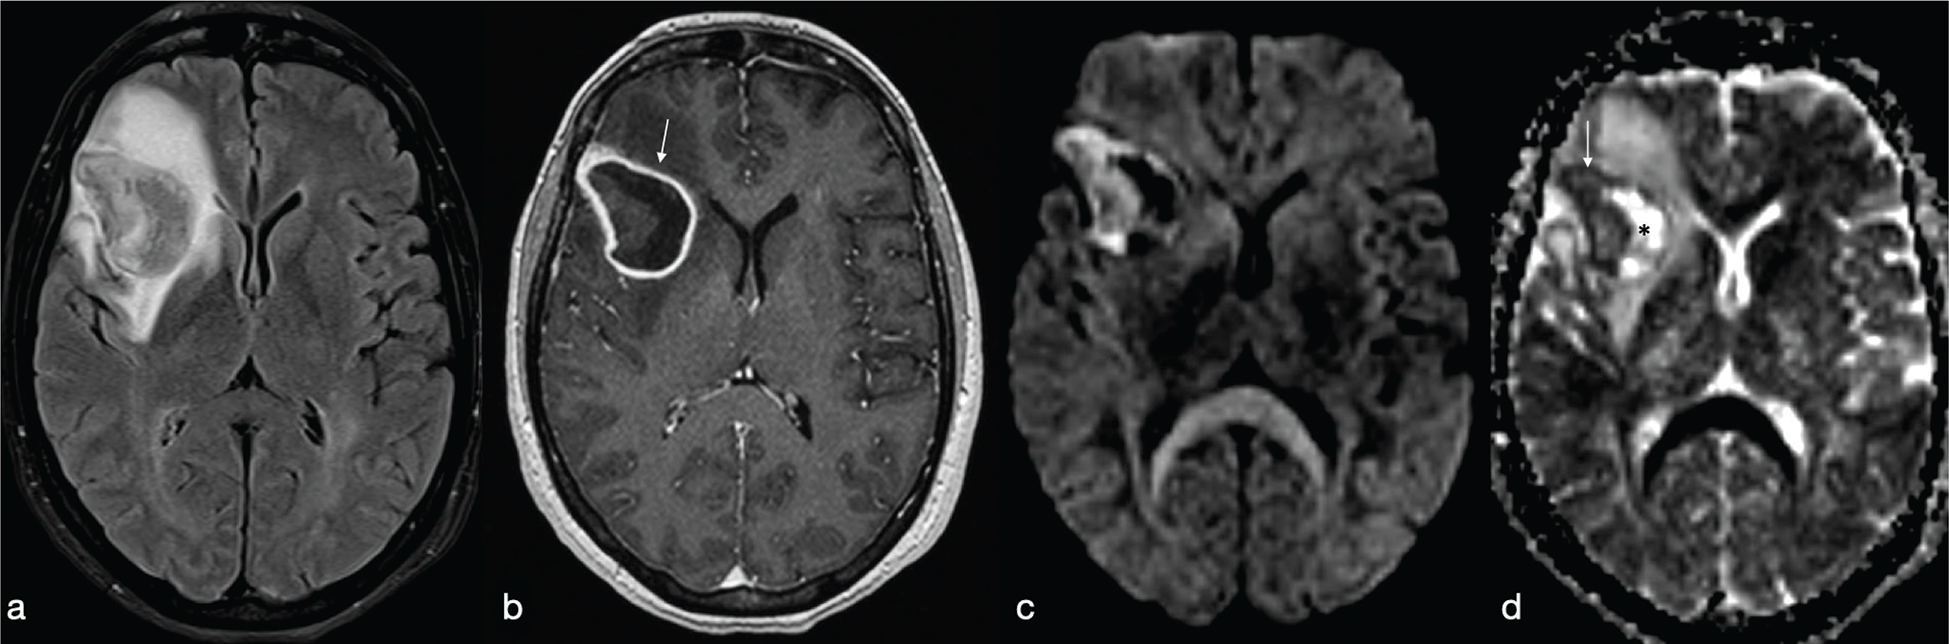

Tuberculous granuloma (tuberculoma) is the most common form of parenchymal CNS tuberculosis. As for pyogenic BA, the cMRI and DWI characteristics depend on the stage of infection: non-caseating, caseating with a solid centre or caseating with a liquid centre (see Table 2). Interestingly, caseating tuberculomas with a liquid centre have an elevated diffusion; indeed, any liquefaction of the central area of necrosis contains a clear fluid, as opposed to pus.7 SWI images may show a complete and regular hypointense peripheral ring.

Tuberculous BA are more similar to pyogenic BA compared to tuberculomas. They usually comprise a multiloculated cavity with central pus, with a thicker wall than a pyogenic BA. It must be distinguished from granuloma with central caseation and liquefaction mimicking pus (Figure 14). However, cMRI does not provide distinction between tubercular and pyogenic BA but lipid peaks without amino acids, on MR spectroscopy, are suggestive of mycobacteria.7

FIG 14. Tuberculoma (a–d) and Tubercular Abscess (e-h). Multiple tuberculomas in both cerebral hemispheres with an hypointense central dot (white arrows in a) within an hyperintense core on T2w are demonstrated. Nodular enhancement on T1+Gd is shown on smaller lesions while the larger one (black arrow in b) shows a thick ring delimitating a cystic core. On DWI and ADC map there is no restricted diffusion (asterisks in c-d). On the contrary, tubercular abscesses located in the quadrigeminal plate show a bright core on T2w, thick peripheral enhancement on T1+Gd (open circle in f) and restricted diffusion on DWI (g) and ADC maps (h).